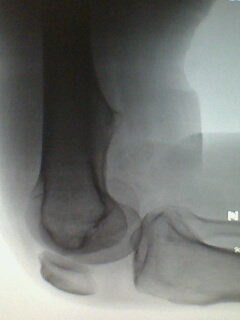

标题: X5658:膝关节改变?!

中年男性,外伤,疼痛!